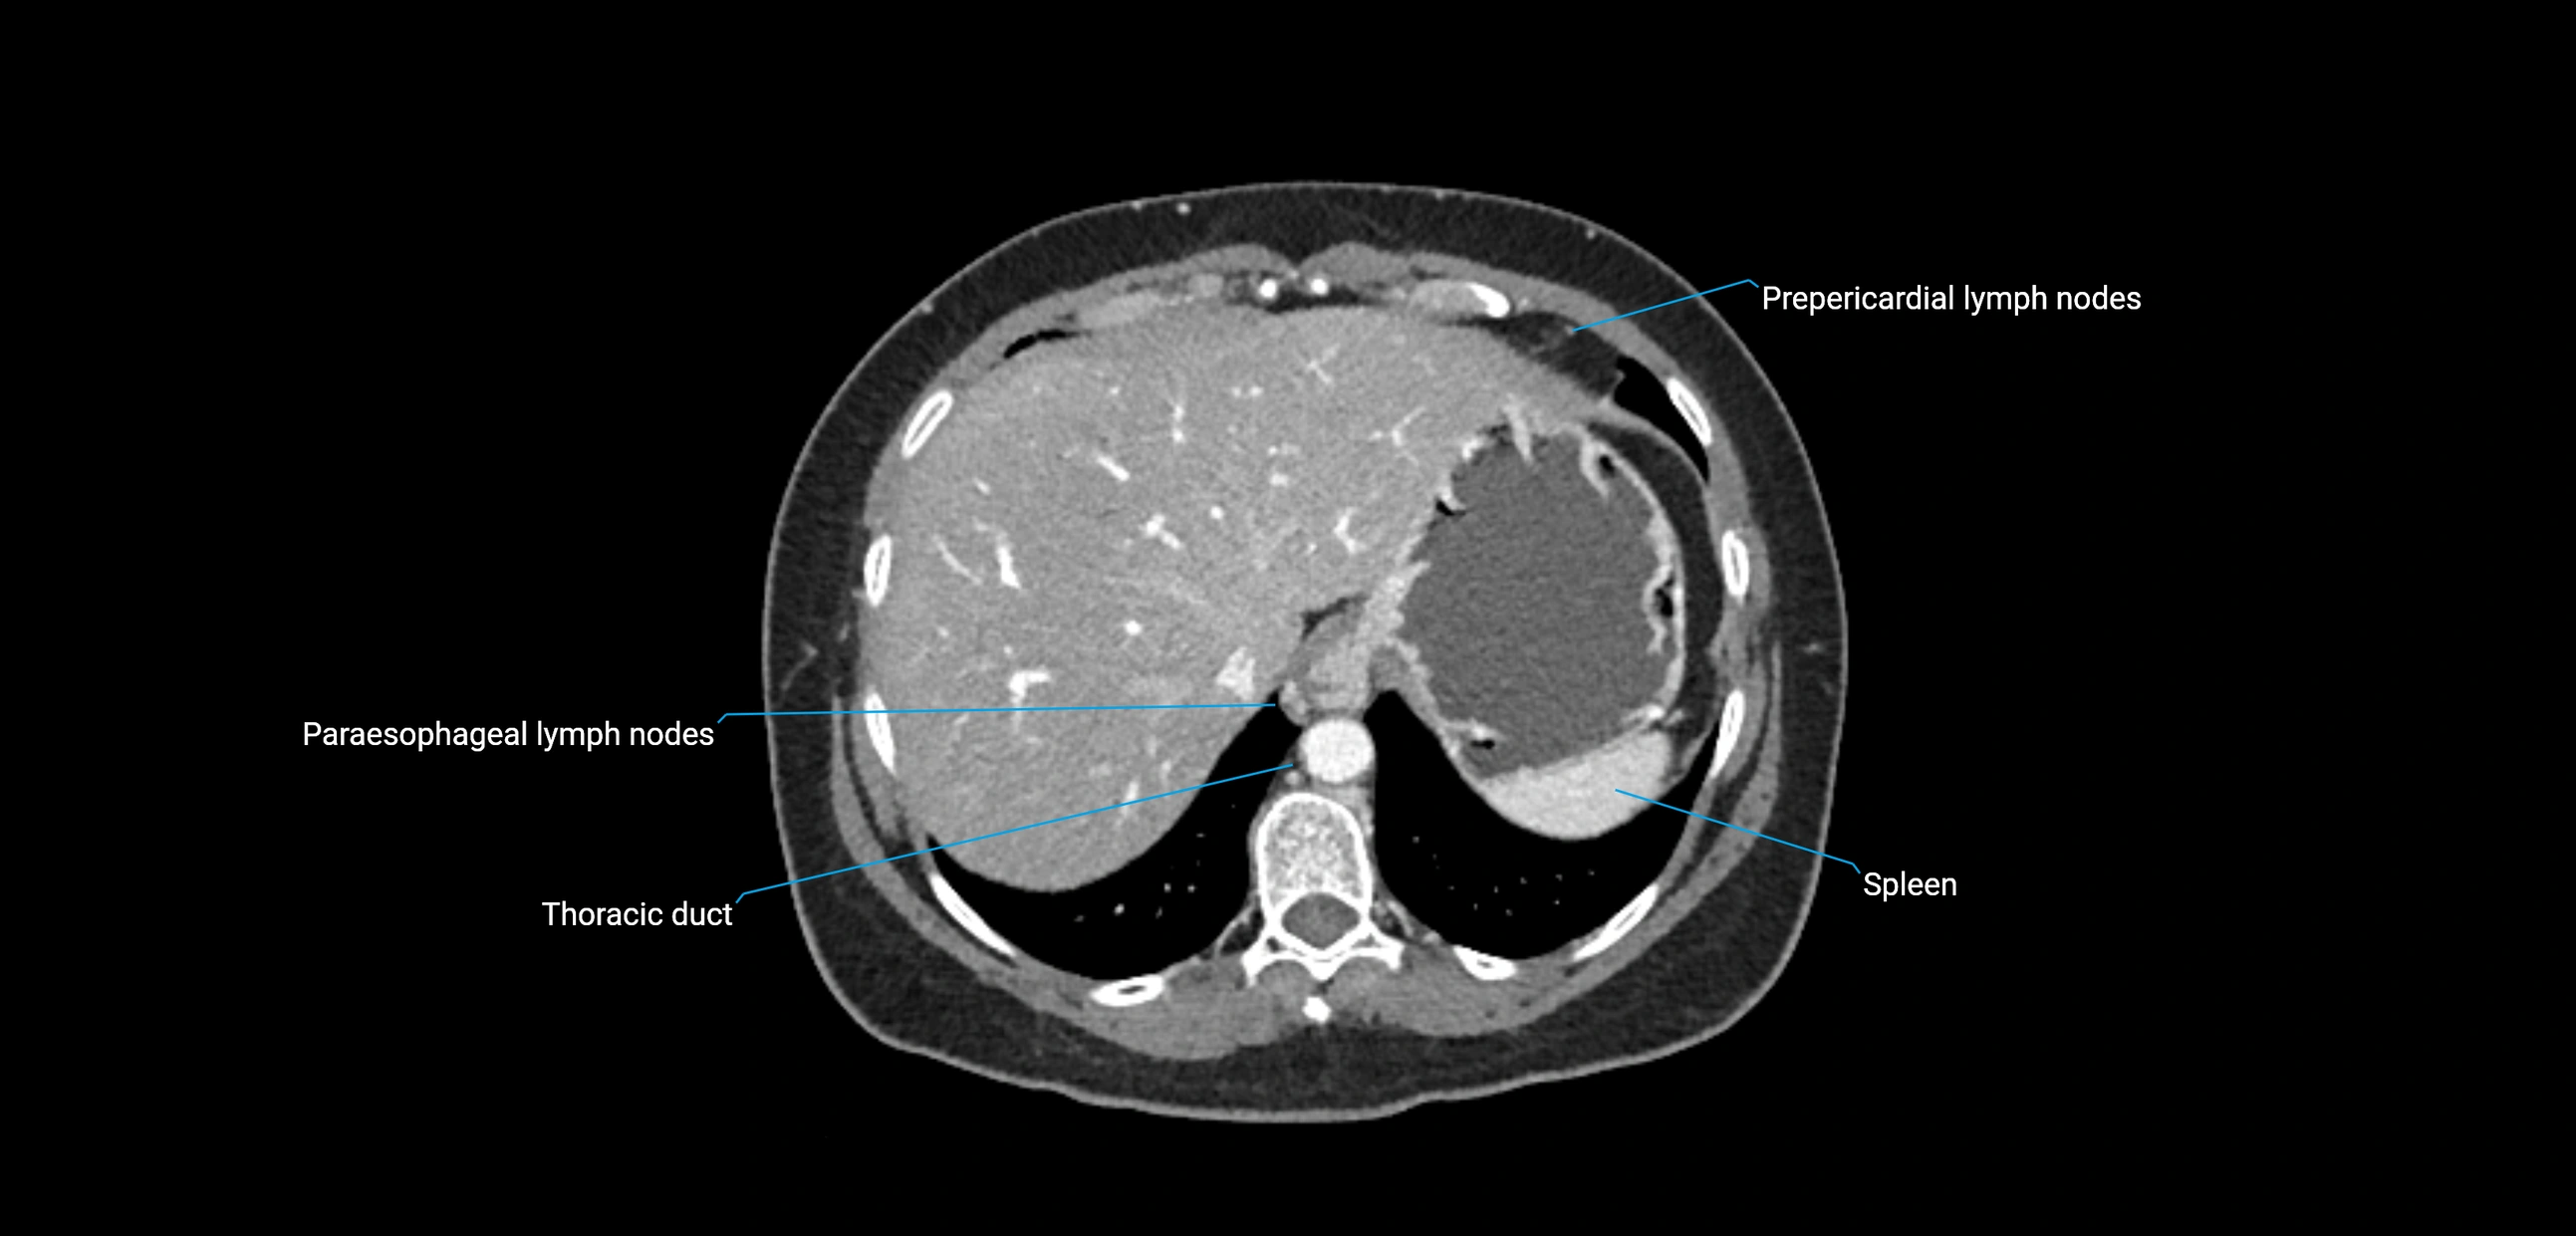

MRI images

image